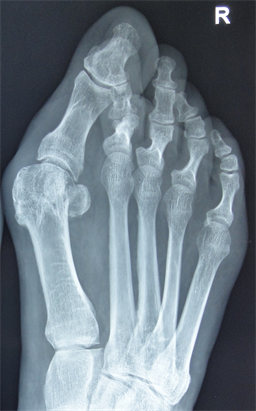

Figure 7. Patient Nr. 2. Hallux valgus with subluxed Ist MPJ and pathological DMAA.

Figure 8. Patient Nr. 2: Correction with 100% lateralization and only point contact of the osteotomy partners.

Figure 9. Patient Nr. 2. Result after 7 years. All components are corrected, no loss of lenght. Immediate full weight bearing, running after 8 weeks.

Figure 10. Patient Nr 2. Clinical appearance before the operation.